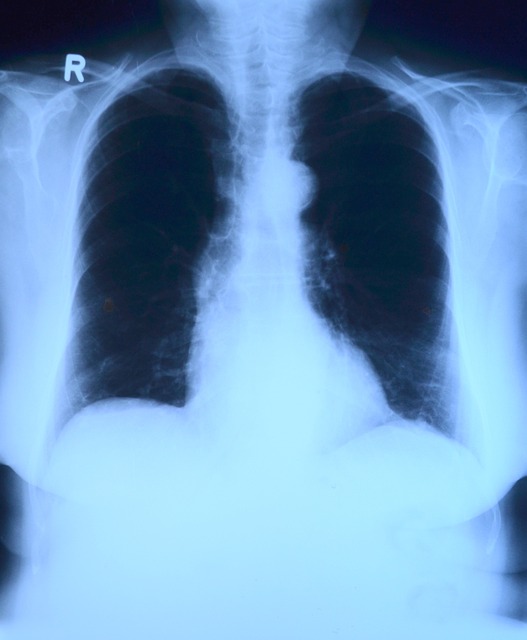

폐암4기란 폐에 발생한 암세포가 림프절을 넘어서 뇌, 간, 뼈, 부신 등 다른 장기로 전이된 상태를 말합니다. 이 시기의 폐암은 수술적 절제가 불가능한 경우가 많으며, 주로 전신적 치료가 중심이 됩니다. 증상으로는 지속적인 기침, 혈담, 흉통, 체중감소, 호흡곤란 등이 나타날 수 있으며, 전이 부위에 따라 다양한 증상을 동반합니다. 폐암4기는 비소세포폐암(NSCLC)과 소세포폐암(SCLC) 두 종류로 나뉘며, 각각의 치료 반응과 예후도 다릅니다. 특히 비소세포폐암은 표적치료제가 가능한 경우 생존율 향상에 기여할 수 있습니다. 2025년 현재 폐암4기의 조기 진단 기술이 진보하면서 환자의 삶의 질을 높이는 방향으로 치료 전략이 세워지고 있습니다.

폐암4기의 평균 생존율은 암의 종류와 환자의 상태, 치료 방법 등에 따라 큰 차이를 보입니다. 2025년 기준으로, 비소세포폐암(NSCLC) 4기 환자의 평균 5년 생존율은 약 8~13% 정도로 보고되며, 면역치료 및 표적치료 병행 시 일부 환자는 장기 생존도 가능해졌습니다. 소세포폐암(SCLC)의 경우 전이가 빠르고 예후가 좋지 않아 평균 5년 생존율이 2~5% 수준으로 낮지만, 최신 면역항암제와 조기 대응 전략으로 개선된 사례도 보고되고 있습니다. 특히, PD-L1, EGFR, ALK 등의 유전자 변이가 있는 환자는 특정 표적치료제를 통해 생존 기간이 유의미하게 연장되고 있습니다. 따라서 생존율은 단순한 수치가 아닌 개인 맞춤 치료와 지속적인 관리로 향상 가능성이 있습니다.